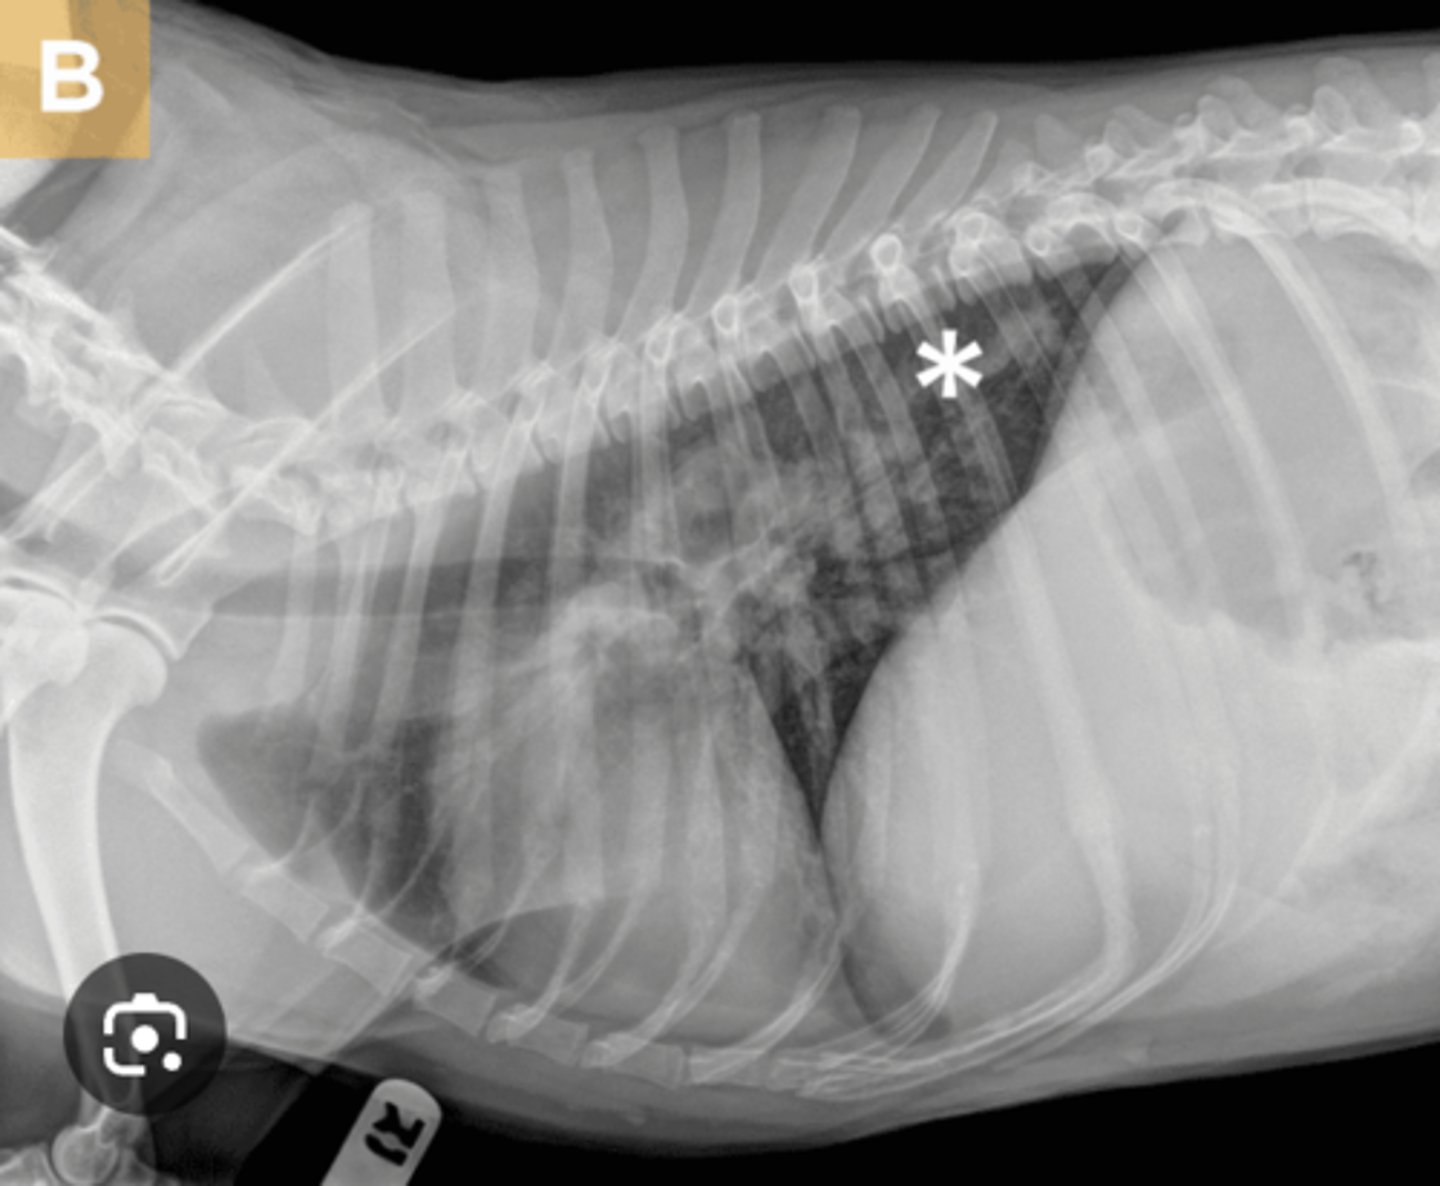

Metastatic disease

Use this image for this question. A 12-year-old canine neutered male patient presents for inappetence, labored breathing, and weight loss. Based on the lung pattern in this thoracic radiograph, and the clinical history, what is your radiographic interpretation?